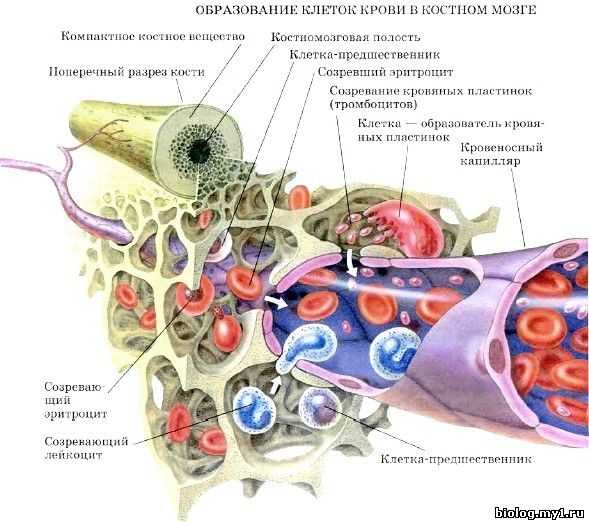

Изучение костного мозга: анатомия и функции